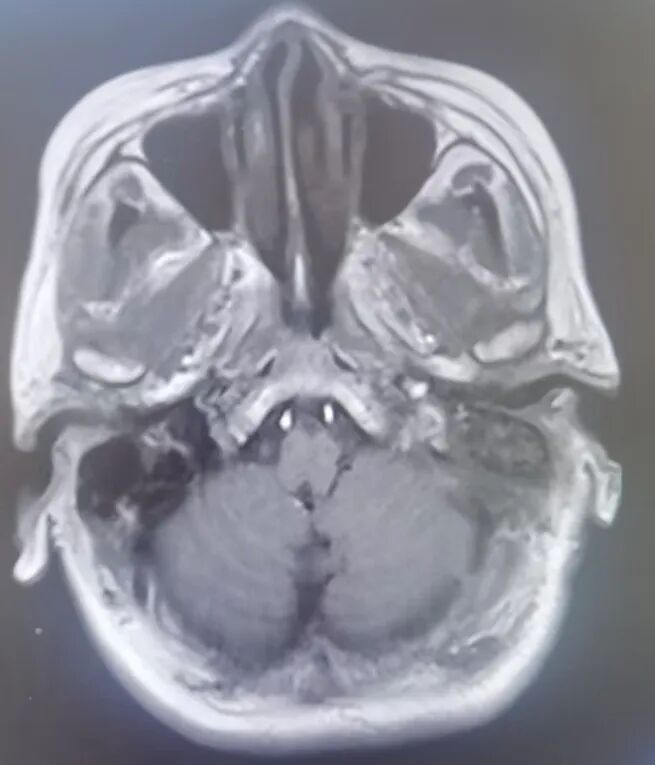

原来,李先生的母亲今年72岁,家住龙口市,一年前在当地医院查体,发现左侧桥小脑角区占位病变,诊断为“听神经瘤”,肿瘤小于2cm,医生建议观察1年后复查。1月前,老人出现了左耳听力下降的临床症状,复查颅脑核磁发现肿瘤有明显生长!

因肿瘤起源于神经的鞘膜,压迫面听神经,术中保留面听神经功能显得尤为重要。手术由耿素民教授亲自主刀,在我院神经外科团队的配合下,术中应用显微镜和神经内镜双镜联合辅助,不磨除内听道骨质便成功将肿瘤全部切除,并完好保留了面听神经功能。

术后第二天,耿素民教授查房,患者恢复良好,听力得到保留,亦无面瘫等常见后遗症发生。看到老人露出了久违的笑容,家人欣喜不已:“俺母亲向来胆小,得知自己脑袋里长了东西,额外增加心理负担,患上了严重的焦虑症,得每天吃药。感谢医院请来这么好的国家级专家,在即墨就给老人做了手术,还这么成功,真是俺们的福气!”

应用双镜联合显微手术切除听神经瘤的优势为: 1.在不磨除内听道情况下,应用神经内镜可观察内听道内全部肿瘤,避免了手术盲区;

3.切除肿瘤后可观察内听道全程情况,避免肿瘤残留,更好地辨认神经走行;